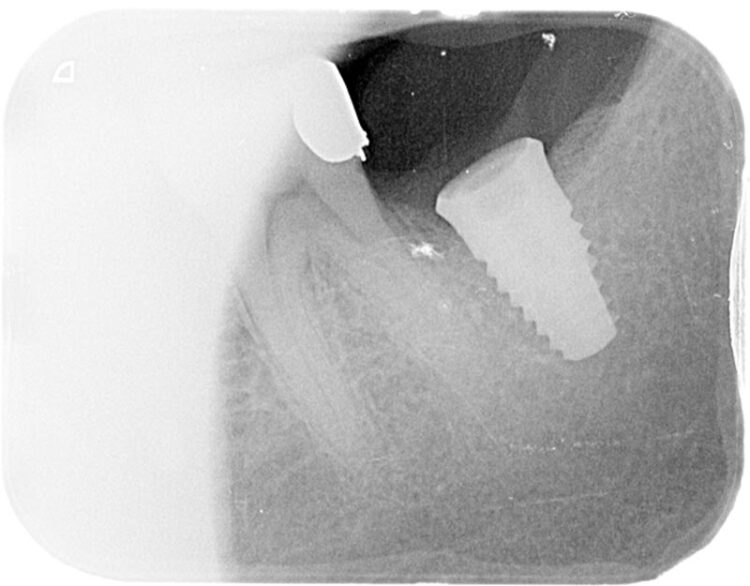

Following three months of healing, a CBCT scan was taken to assess bone dimensions and proximity of nearby anatomical landmarks, namely the inferior dental nerve and the lingual undercut of the mandible.

3-D radiographic examination showed sufficient bone available for the placement of a 5.8mm x 9mm BioHorizons Camlog tapered tissue level implant. Surgical placement of this implant involved a two-sided flap and there was no need for hard or soft tissue augmentation. The implant was placed with excellent primary stability and therefore a single-staged approach was followed with a healing abutment being placed at implant placement.

The implant was then left to heal and integrate for three months. No temporary prosthesis was required during this phase.